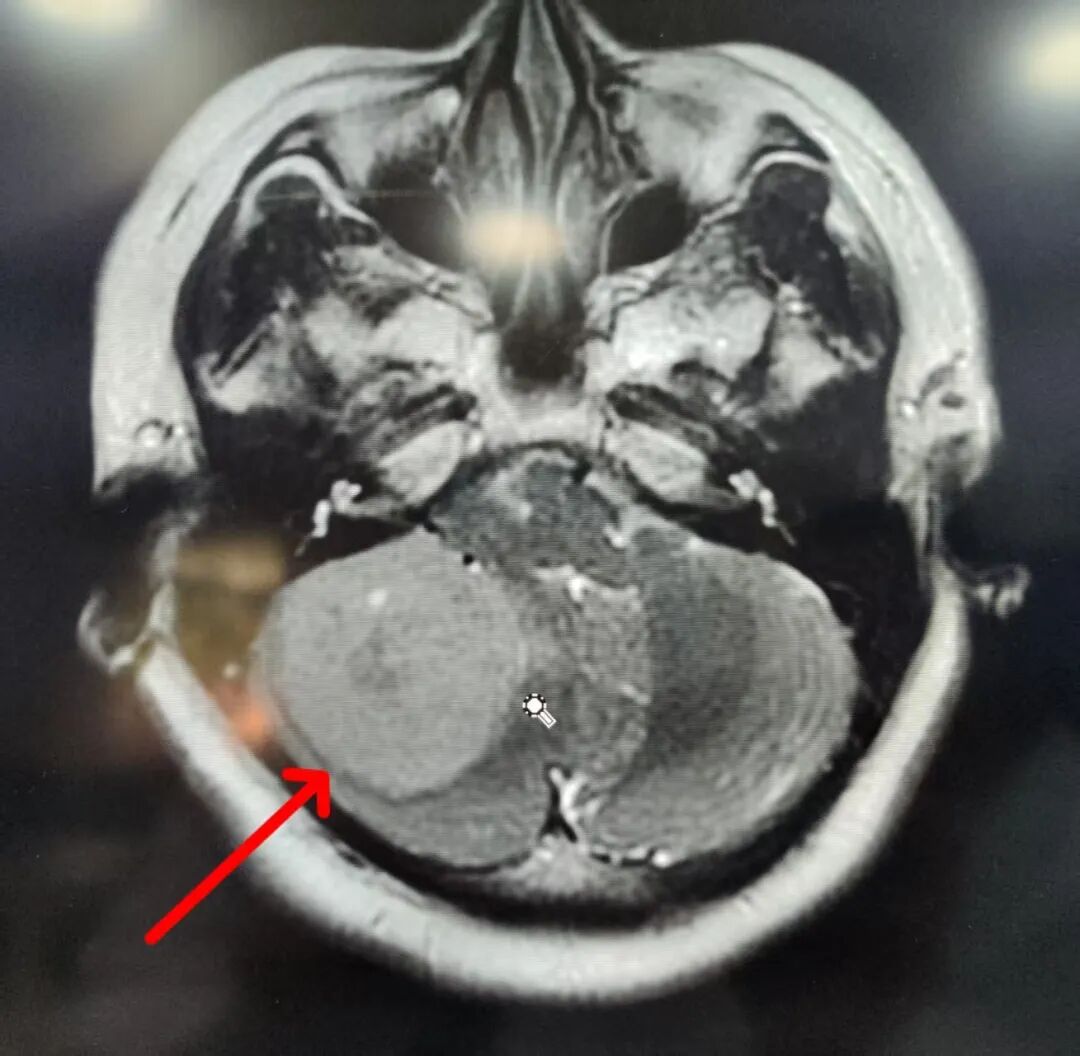

50岁的张阿姨(化名)近1个月来出现阵发性头痛、头晕,经检查发现右侧后颅窝占位性病变,且肿瘤已压迫邻近脑组织,导致脑水肿和颅内压增高,进而影响脑干功能。脑干作为控制心跳、呼吸和血压的关键部位,任何损伤都可能直接威胁患者生命。

术中,手术医生发现肿瘤质地韧、血运丰富,与周围脑组织紧密粘连。在显微镜辅助下,手术医生以毫米级精度细致分离肿瘤与神经,最终将约50*45*20mm的巨大肿瘤完整切除。

(▲术前核磁共振)